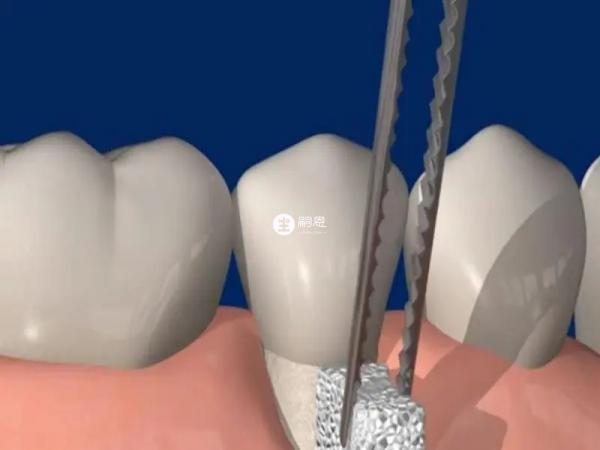

患者要是拔除智齿烂牙根,那就需要经过切开、翻瓣、去骨、缝合等手术操作,操作起来还是比较麻烦的,这个手术也是比较考验医生的技术的,所以过程比较复杂。

烂牙根如果没有完全龋坏是可以进行修复的,此时就不用强行拔牙根,但在修复前需要根据具体情况,是否需要处理神经,做根管治疗,保留牙根,利用牙根做桩冠修复,或者是做覆盖义齿修复。